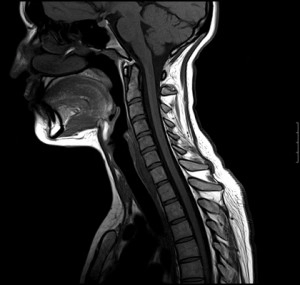

МРТ шеи

Существует немало заболеваний, при которых самым информативным и безопасным исследованием является МРТ мягких тканей шеи.

Получаемые изображения наиболее точно и явственно визуализуют различные патологии, которые сложно обнаружить и идентифицировать при обычном наружном осмотре.

Последовательное сканирование в различных ракурсах позволяет воссоздать при помощи компьютера объемную модель исследуемого участка.

Изображения, полученные при помощи томографа, позволяют оценить состояние позвонков и позвоночных дисков, спинномозгового канала и спинного мозга, мягких тканей шеи, кровеносных сосудов. При обследовании обнаруживаются новообразования в мягких тканях и костях, ишемические и воспалительные очаги, грыжи, расслоения тканей, абсцессы, метастазы и другие патологии, которые невозможно обнаружить при наружном осмотре.